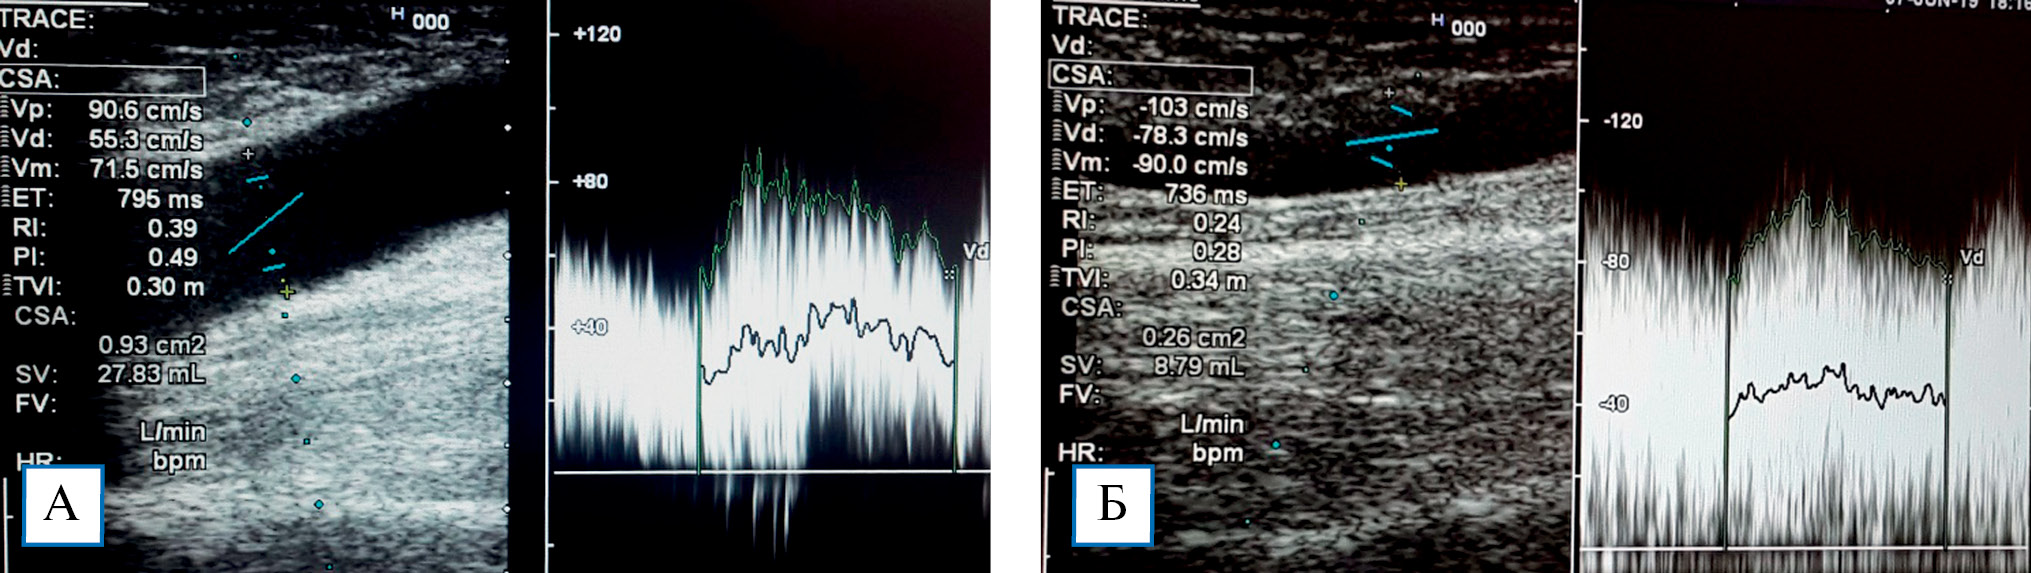

При пробе с физической нагрузкой у пациентов без стил-синдрома наблюдалось увеличение показателя ОСК на 29,3 ± 4,6% (рис. 3). Снижение тонуса резистивных сосудов при физической нагрузке способствует увеличению притока крови в микроциркуляторное русло кисти, что является важным механизмом ауторегуляции кровотока и адаптации к гипоперфузии. При стил-синдроме в ответ на физическую нагрузку реакция отсутствовала, что указывает на срыв компенсаторных механизмов регуляции кровотока в кисти (рис. 4).

Рис. 3. Эхограммы локтевой артерии: объемная скорость кровотока исходно (А) составила 610 мл/ мин, после пробы с физической нагрузкой (Б) — до 868 мл/мин (увеличение на 30,0%)

Рис. 4. Эхограммы локтевой артерии: объемная скорость кровотока исходно составила 425 мл/мин (А), ее снижение после пробы с физической нагрузкой до 417 мл/мин свидетельствует о срыве компенсаторных механизмов ауторегуляции кровотока в кисти (Б)